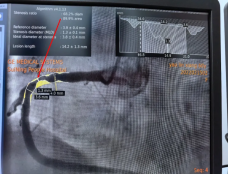

当天开展的两台手术中:病例1为36岁男性患者,因反复胸痛3年,再发20天来院求诊,经完善心电图等相关检查,予以行冠状动脉造影,排除冠心病、心绞痛致病可能。病例2为 60岁女性患者,既往有冠心病支架植入术病史,此次因胸痛不适来院治疗。经行冠状动脉造影,发现其右侧冠状动脉近中段有一处89.9%的血管狭窄,术中在征得患者及家属同意后,立即予以行冠状动脉支架植入术。术后患者生命体征平稳,截止目前未再复发胸痛。

支架植入术前 术后